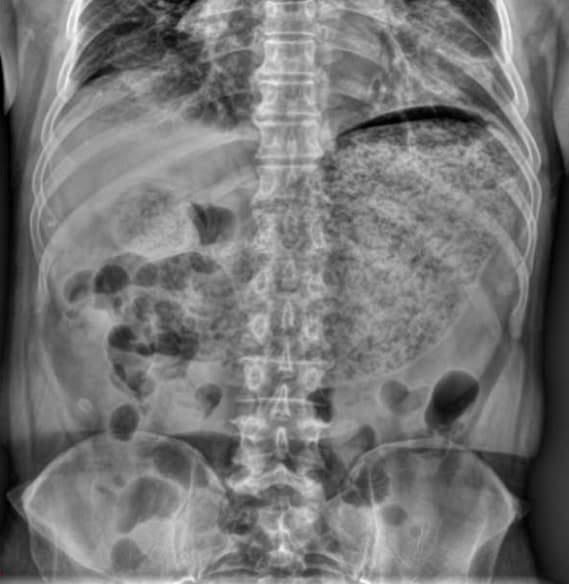

La gastroparésie est un trouble de vidange gastrique. Elle se produit lorsque les nerfs de l'estomac sont lésés. La régulation du mouvement des aliments dans l'appareil digestif (péristaltisme) est empêchée : la progression des aliments est alors ralentie, voire stoppée, ce qui implique une vidange gastrique plus longue. Il s'agit d'une complication du diabète de type 1 (20 % des diabétiques de type 1). On la rencontre également, mais moins souvent chez les personnes atteintes de diabète de type 2. Les autres causes sont les suites d'une chirurgie gastrique, une maladie de Parkinson, ou un Syndrome d'Ehlers-Danlos. Elle n'a pas d'explication dans plus d'un tiers des cas (« gastroparésie idiopathique »). Elle peut entraîner des nausées ou des vomissements alimentaires, une perte d'appétit, des ballonnements ou des douleurs abdominales. Son évolution est sur le mode cyclique pour certains avec des phases d'amélioration suivies d'une exacerbation, tandis que d'autres vivent avec des symptômes quotidiens. Le temps de vidange gastrique peut être estimé par une scintigraphie : un traceur radioactif est ingéré en même temps qu'un repas et une imagerie abdominale est faite à plusieurs temps, jusqu'à 4 h après. Une variante consiste à déterminer le temps où un traceur ingéré arrive dans l'air expiré. Il existe également des capsules électroniques qui peuvent être avalées et enregistrer différents paramètres. La Société américaine de gastro-entérologie a publié des recommandations sur la prise en charge des gastroparésies en 2013. Dans les formes sévères, une réhydratation ainsi qu'une correction des troubles électrolytiques est nécessaire. Plusieurs mesures diététiques peuvent parfois améliorer les symptômes : repas fractionné ou plus long, pauvre en graisses, sans caféine, alcool ou tabac, avec une promenade « digestive ». Le métoclopramide et le dompéridone améliorent les symptômes de la gastroparésie du diabétique. Les antidépresseurs tricycliques ont une certaine efficacité dans la dyspepsie mais pas dans la gastroparésie.